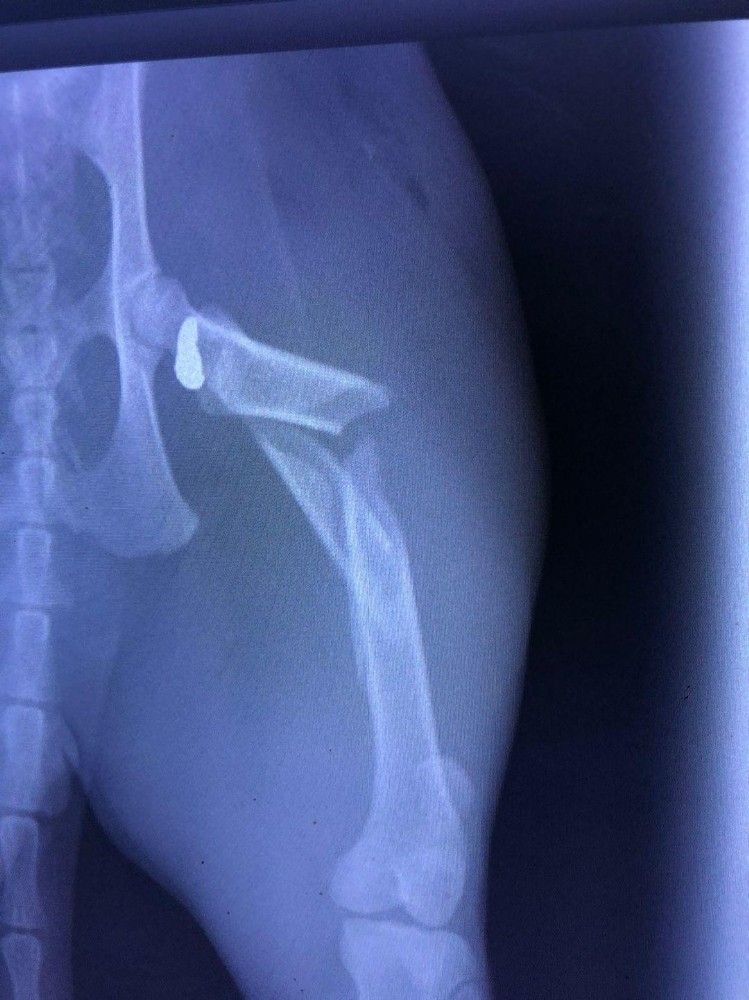

Kedinin sahibi Defne Bardakçı, "Kedimizin vurulduğunu fark edince hemen veterinere götürdük. Ameliyat için bizi Gökova Hayvan Hastanesine yönlendirdiler. Vücudunda 6 kırık tespit edildi. Hayvan hastanesinde gerçekleştirilen ameliyatla saçma çıkarıldı. Sokağa çıkma yasağında kedimiz dışarıda geziyordu. Datça gibi hayvansever bir ilçede böyle bir şey yaşamak bizi hem şaşırttı, hem de üzdü. Havalı tüfekle vurulduğu için sesi duymadık. Kedimiz eve yaralı halde kanlar içinde gelince şoke olduk" dedi.